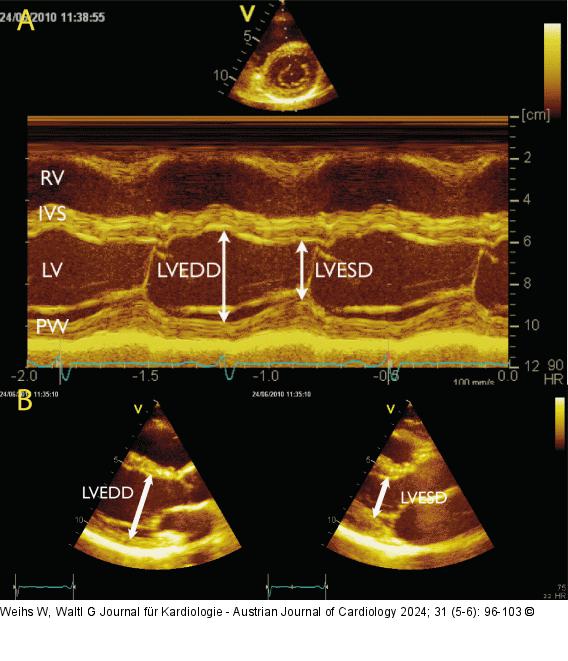

Abbildung 3: Echo Messung der enddiastolischen und endsystolischen Diameter des linken Ventrikels aus dem M-Mode (A) und B-Bild (B). Der M-Mode kann aus dem parasternalen Längs- oder Querschnitt generiert werden. |

Messung der enddiastolischen und endsystolischen Diameter des linken Ventrikels aus dem M-Mode (A) und B-Bild (B). Der M-Mode kann aus dem parasternalen Längs- oder Querschnitt generiert werden. |